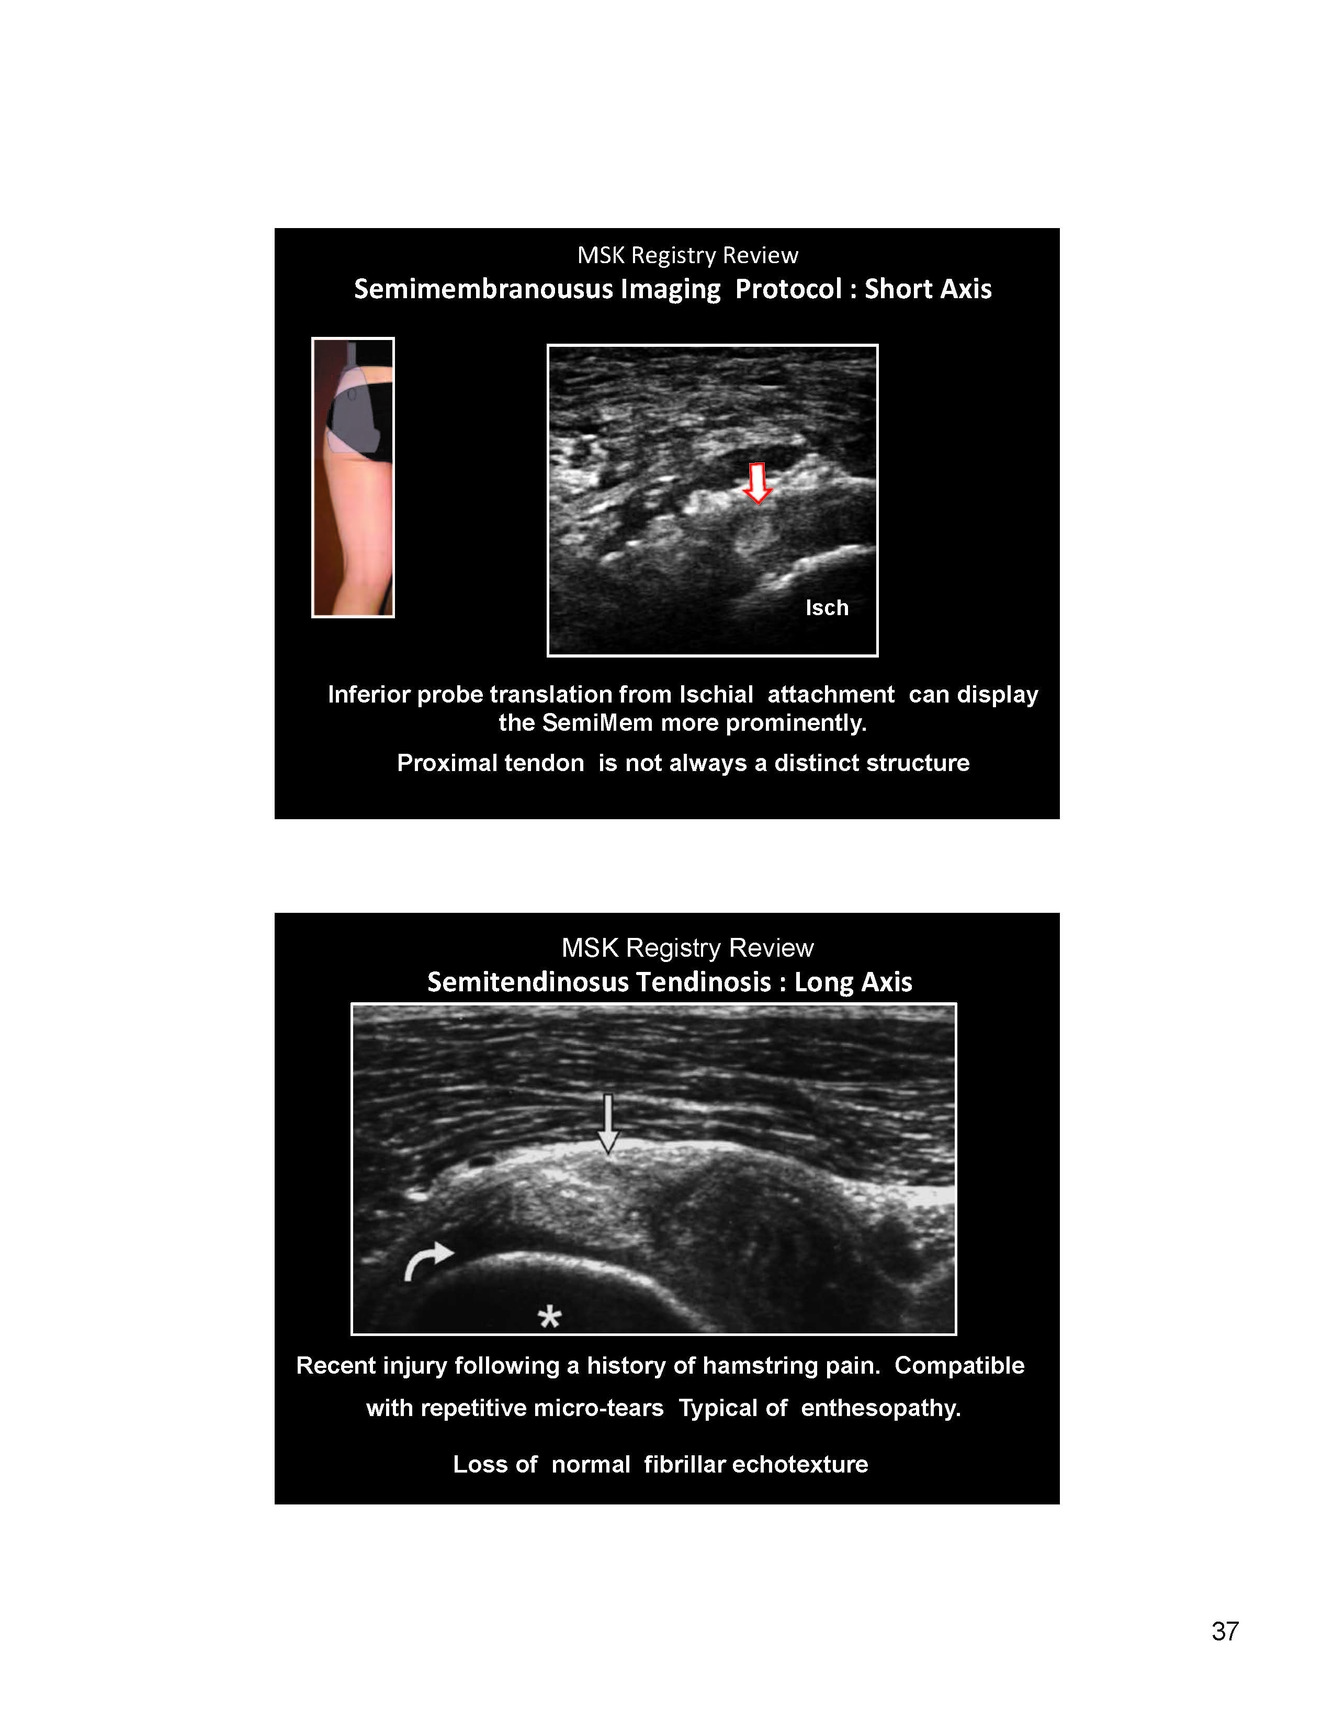

Image of semimembranosus

moving probe inferior translation for Ischial attachment